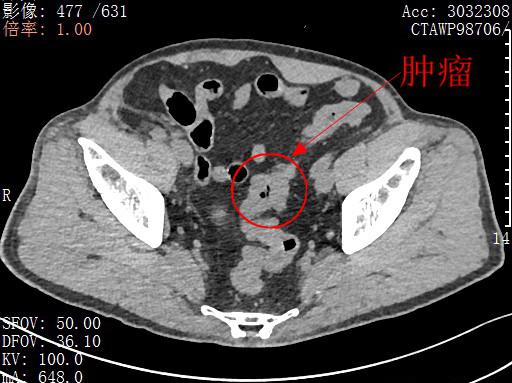

了解到程先生的顾虑后,北大深圳医院胃肠外科主任吕国庆率团队对程先生的病情进行了评估:肿瘤位于乙状结肠,肿瘤分期属于中期,大小约 3 厘米 ×2 厘米,距肛门 35 厘米。在评估了患者移植肾的功能及术后可能发生的肾损伤概率之后,经过仔细讨论,医生团队认为可以为患者实行腹腔镜微创 NOSES 手术。